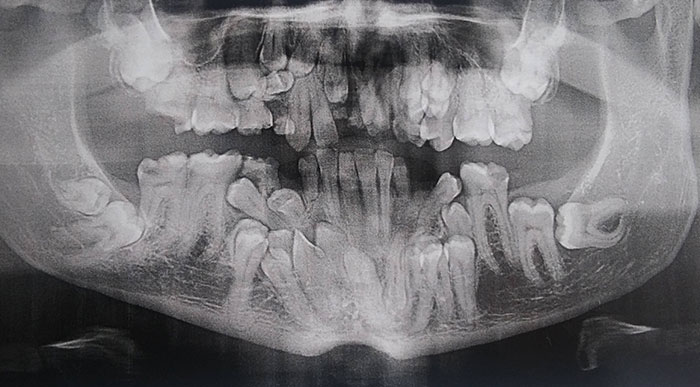

I Have A Rare Disorder Called Cleidocranial Dysotosis. Got My First Dental X-Ray Today And I Have A Lot Of Extra Teeth

X-Rays Of Children's' Mouths Between The Ages Of 6-12 Years Still Hold Wonder For Me, Even After Being A Dentist For 10+ Years

Panoramic X-Ray Of A Child (Adult Teeth Growing In)

Today I Took A Dental X-Ray For A Child. This Is How The Milk Teeth Change Permanently. The Picture Clearly Shows How The Premolar Comes Out

Dental 3D X-Ray On A Child

The Extra Row Of Teeth In The X-Ray Of My 7-Year-Old Kid